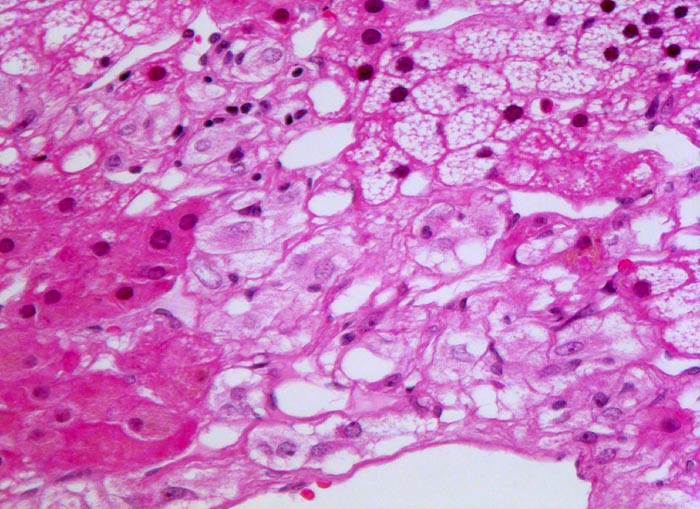

Phaeochromozytom

Basophile Tumorzellen, welche an normales Nebennierenmark erinnern infiltrieren die Zona fasciculata ( lipidreiche Zellen mit vakuolisiertem Zytoplasma) und die Zona reticularis ( lipofuscinhaltige Zellen).

Der Patient klagt über rezidivierende Kopfschmerzen seit zirka zwei Monaten. In letzter Zeit hat er Alcacyl genommen, jedoch ohne Erfolg. Die Computertomographie des Abdomens zeigt einen 5cm grossen Tumor im Bereich der rechten Nebenniere. Die Familienanamnese für multiple endokrine Neoplasien (MEN) ist bland.